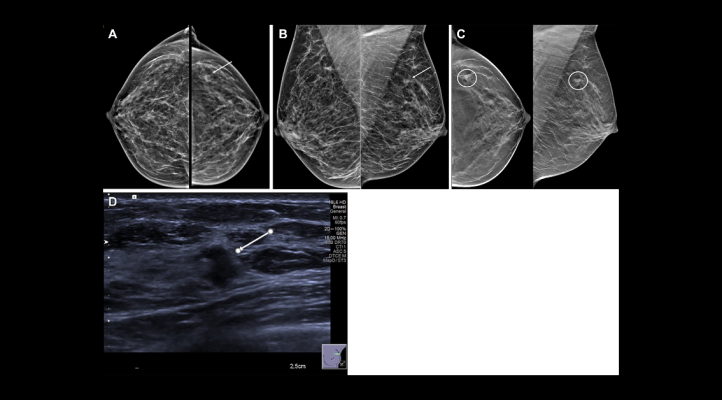

Images in a 54-year-old woman show a palpable lump in the right breast and an irregular mass in the left breast. Mammographic evaluation of the right breast was normal. (A, B) Craniocaudal (A) and mediolateral oblique (B) views of synthesized mammograms and (C) tomosynthesis image in craniocaudal and mediolateral oblique view of the left breast show an architectural distortion with mass (arrow in A and B, circles in C). (D) Targeted US scan at the site of the incidental finding shows an 8-mm hypoechogenic irregular solid mass with indistinct margins (arrow). US-guided biopsy showed invasive ductal carcinoma, grade I. Image courtesy of RSNA